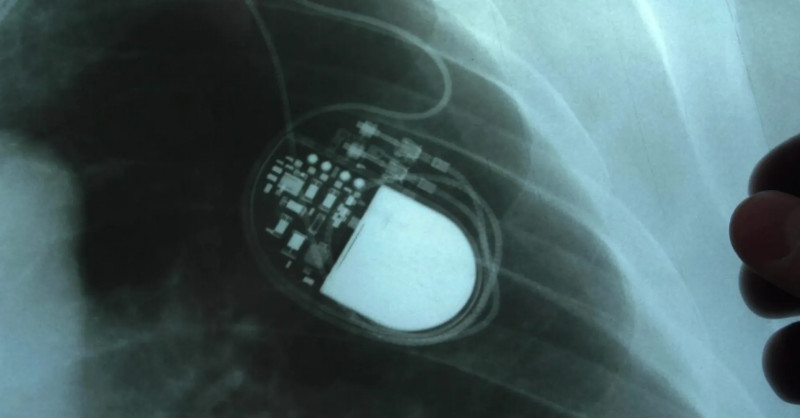

Ministerstvo zdravotnictví podalo trestní oznámení na Fakultní nemocnici Olomouc kvůli podezření z obcházení indikačních kritérií při implantaci kardioverterů-defibrilátorů, což může vést k podvodu a těžkému ublížení na zdraví stovek pacientů. #zdravotnictví #defibrilátory #vyšetřování

Ministerstvo zdravotnictví podalo trestní oznámení kvůli podezřelým operacím s implantacemi kardioverterů-defibrilátorů ve Fakultní nemocnici Olomouc, což vyvolalo policejní vyšetřování zaměřené na možné obcházení indikačních kritérií a těžké ublížení na zdraví stovek pacientů. #Zdravotnictví #TrestníOznámení #Defibrilátory

Ministerstvo zdravotnictví podalo trestní oznámení kvůli závažným podezřením na manipulaci s dokumentací a obcházení kritérií při implantacích defibrilátorů ve Fakultní nemocnici Olomouc, na což jako první upozornily Seznam Zprávy v loňském prosinci. #zdravotnictví #defibrilátory #bezpečnostpacientů

Ministerstvo zdravotnictví podalo trestní oznámení v souvislosti s kauzou defibrilátorů na I. interní klinice Fakultní nemocnice Olomouc, kde interní dokumenty naznačují možné obcházení indikačních kritérií a manipulaci se zdravotnickou dokumentací, a to na základě závažných podezření o neoprávněném čerpání prostředků z veřejného zdravotního pojištění. #zdravotnictví #defibrilátory #trestníoznámení

Interní audit ve Fakultní nemocnici Olomouc odhalil závažné nesrovnalosti v dokumentaci pacientů zapojených do mezinárodní studie zaměřené na defibrilátory, kdy pouze u dvou z přibližně 70 pacientů byla shoda mezi studijními údaji a nemocničním systémem, a případ nyní vyšetřuje policie pro podezření z podvodu a těžkého ublížení na zdraví. #zdravotnictví #audity #defibrilátory